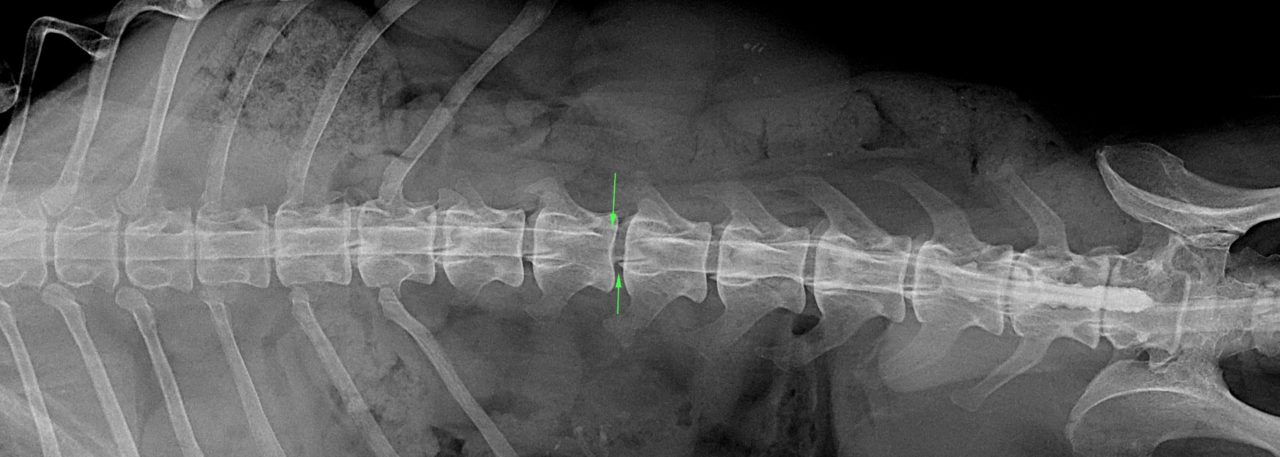

では、「犬の椎間板ヘルニア」とは、具体的にどんな病気なのでしょうか? この病気を説明するには、椎間板の説明をする必要があります。 まず、「椎間板」とは、一般的に犬の背骨と背骨の間にクッションのように挟まっている「クッション材のような組織」の事を言います。 そして、「ヘルニア」とは、そのクッション材が、何らかの原因で「グシャ」っと潰れて変形してしまっ 犬の椎間板ヘルニアで針治療について検討されている方は、参考にしてください。 そもそも針治療って何をしているの? 第一段階 まず深い部分のコリをほぐす 第二段階 マヒした部分の「目を覚ます」 最終段階 体を動かす感覚を取り戻す。 犬の椎間板椎間板ヘルニア(胸腰椎) >>>犬の胸腰部の椎間板ヘルニアとは? 正常な 椎間板 は左下の図のように 椎骨 (背骨)の骨と骨の間に存在し、中心にあるゼリー状の 髄核 と、この 髄核 を取り巻く 線維輪 で構成されており、背骨に加わる圧力を吸収

椎間板ヘルニアの治療 椎間板ヘルニアの治療は大きく分けて内科療法と外科療法に分けられます。 内科療法 内科療法は脊髄の圧迫の軽度な子、症状の軽い子に対しておこなわれます。ただし、ダックスのような軟骨異 犬の神経疾患でも最も多いのが 椎間板ヘルニアです。 症状は、痛みや後ろ足のふらつきなど の軽いものから、自力で立ち上がる ことができなくなる重症のものなど さまざまです。 治療法についてはグレ